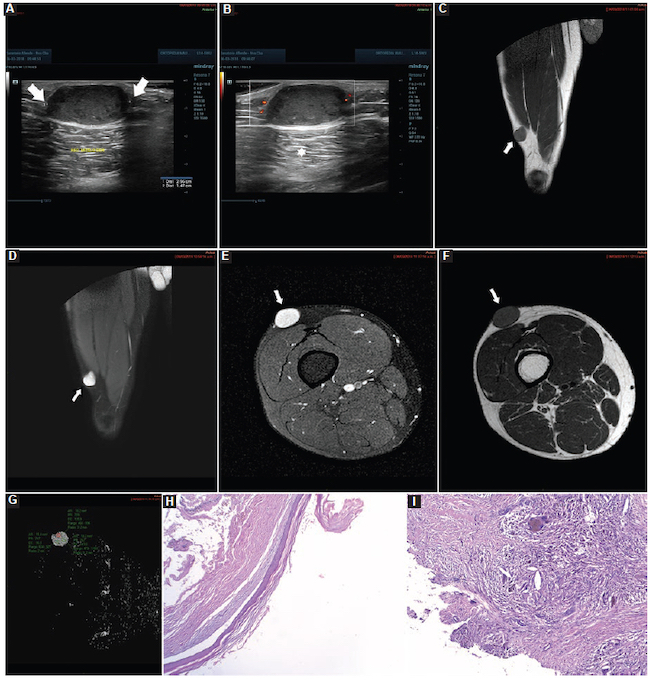

Para las biopsias se utilizaron agujas dedicadas para cada tejido. Cuando las lesiones fueron de partes blandas se procedió con guía ecográfica con un equipo Mindray Resona 7 (Mindray Headquarter, Shenzhen, República Popular de China), con transductor de alta frecuencia, y se utilizaron agujas de corte tipo Tru-Cut de 14 o 16 G con una longitud de 10 cm (dependiendo del tamaño de la lesión), montadas en una pistola de disparo automático a doble armamento (Fig. 2). Cuando las lesiones fueron óseas se procedió con guía tomográfica con un equipo Siemens Somatom Sensation de 64 Canales (Alemania, Erlangen) y se utilizaron agujas de punción ósea para médula ósea de 11 × 4 G (Fig. 3).

Lipomas: fueron nueve casos, con un valor medio de CDA de 1,66 ± 0,31 × 10−3 mm2/s (1,30-2,10) (Fig. 10), de los cuales fueron cuatro en los miembros superiores, cuatro en los miembros inferiores y uno adyacente a la parrilla costal.

Sarcomas: fueron 19 casos, con un valor medio de CDA de 1,33 ± 0,57 × 10−3 mm2/s (0,70-2,60) (Fig. 14), de los cuales fueron ocho sinoviales, cuatro fusocelulares, tres fibromixoides, dos pleomórficos y dos epitelioides.